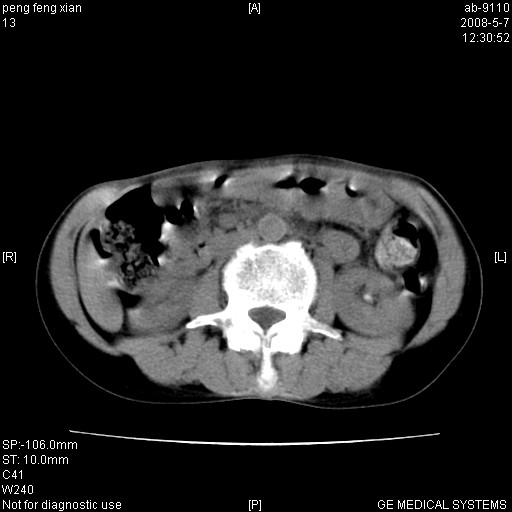

女,56岁。b超左一腹包块,考虑胃肠道肿瘤。

胃底占位待出;右肾结石?

胃体部胃壁增厚,不均匀性强化,与胰腺分解欠情.

考虑:胃癌,胰腺受侵待除外.